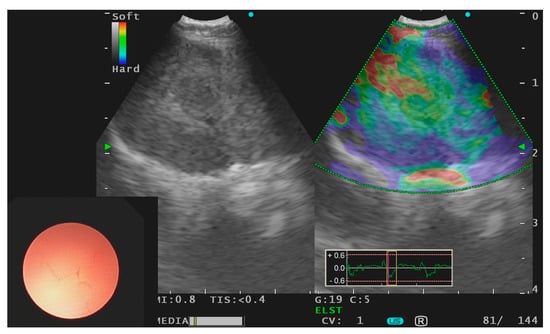

- Fujiwara, T.; Nakajima, T.; Inage, T.; Sata, Y.; Sakairi, Y.; Tamura, H.; Wada, H.; Suzuki, H.; Chiyo, M.; Yoshino, I. The combination of endobronchial elastography and sonographic findings during endobronchial ultrasound-guided transbronchial needle aspiration for predicting nodal metastasis. Thorac. Cancer 2019, 10, 2000–2005. [Google Scholar] [CrossRef] [Green Version]